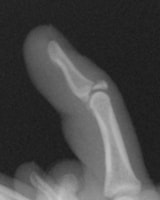

高精細デジタルX線イメージ

整形外科領域の手術において、骨を扱う際に必要なのがX線イメージです。当院では米ホロジック社製のフルオロスキャンを用いることにより、一般整形外科で用いる巨大なCアームでは見ることが困難な指骨の関節内骨折においても良好な整復操作を行うことを可能としています。